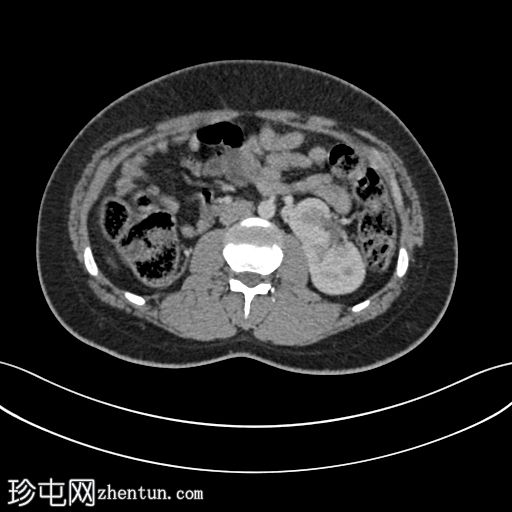

轴位肾排泄期

轴位CT图像显示双肾位于腹部左侧,肾实质融合,符合交叉融合性肾异位。延迟期图像证实双侧输尿管均正常开口于膀胱,右侧输尿管跨越中线开口于右侧膀胱输尿管连接处。